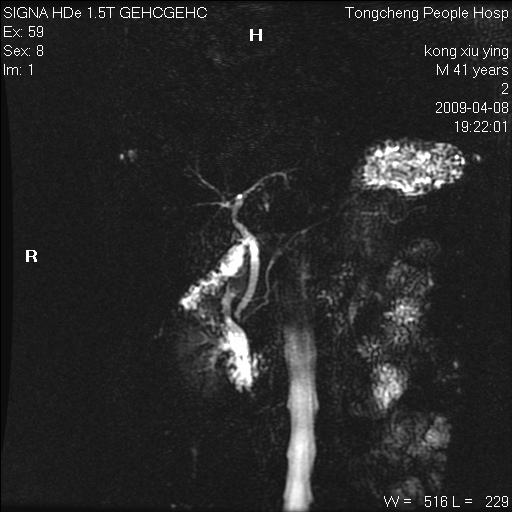

标题: CL1008:【经典】胆囊石榴籽样结石。

女,41岁。健康体检——彩超提示:胆囊显示不清。平素健康,无不适感。

腹部mr扫描及mrcp,图像如下: